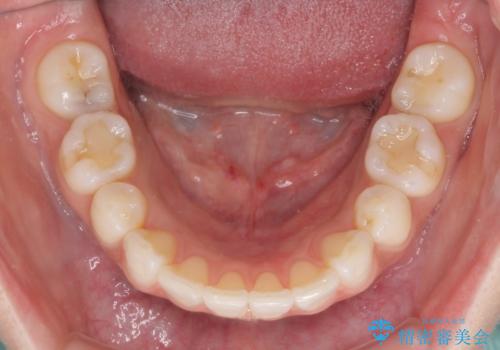

矯正治療の後戻り インビザラインによる再矯正治療

デコボコが解消されるのはもちろんのこと、突出感のあった前歯を引っ込めることができ、患者様には大変満足していただきました。